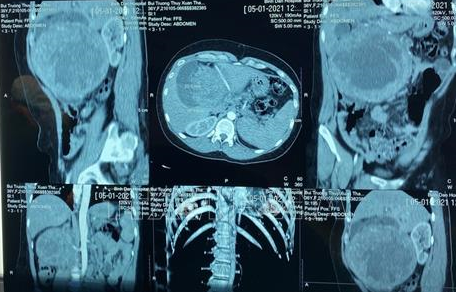

| Ảnh minh họa: Đinh Hằng/TTXVN |